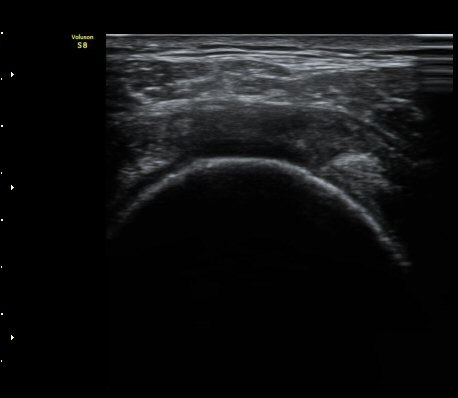

3°³¿ù ÈÄ ÃßÀû°Ë»ç

2049205267_a5fe3a8a_US181253111.jpg